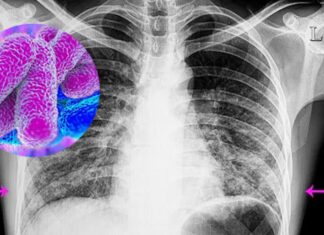

Aumentaron otra vez los casos de covid y hubo 4 fallecimientos